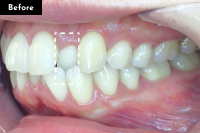

Basicプラン

上下前歯12本の部分矯正

20代 女性

治療費用:Basic 33万円(税込)

治療期間:4ヶ月

- Before

After